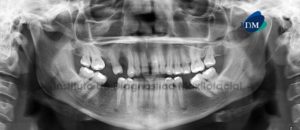

Paciente masculino de 27 años de edad acude al Instituto de Diagnóstico Maxilofacial por evaluación de terceras molares. Motivo por el cual se le realiza